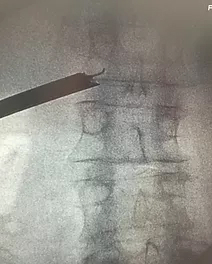

Эндоскоп установлен в область локализации фораминальной грыжи на уровне L2-L3.

Установка эндоскопа и доступ к позвоночной грыже осуществляется под рентген-навигацией в двух проекциях, что обеспечивает максимальную безопасность оперативного вмешательства.